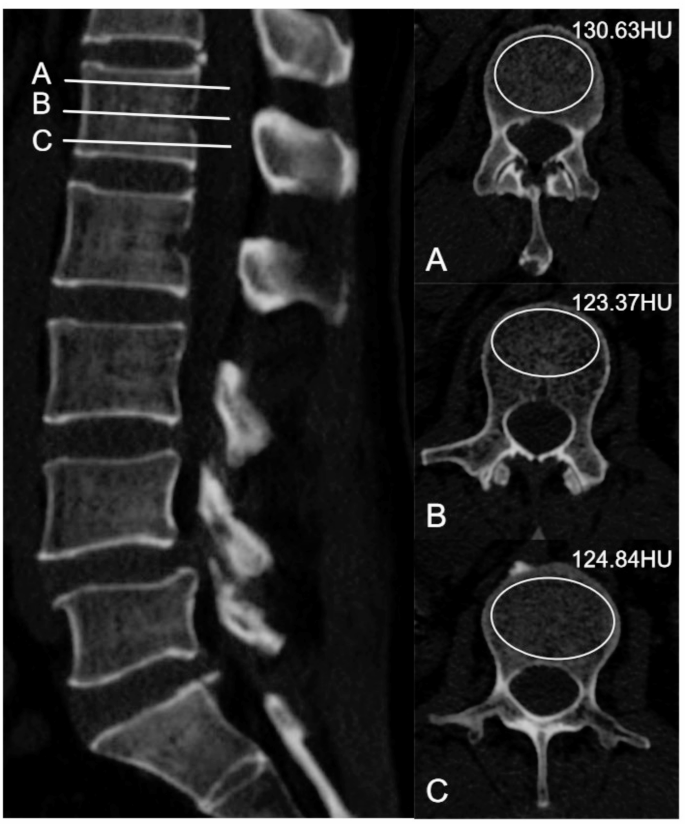

CT attenuation values and classification

CT attenuation values measurement10: The CT attenuation values of each vertebral body from L1 to L5 were assessed using PACS. Measurements were taken at three sites below the upper endplate, central cancellous bone, and lower endplate. Care was taken to avoid cortical bone, osteophytes, and non-cancellous areas (Fig. 1). The CT attenuation values were obtained by averaging measurements from three professional spinal surgeons.

The method for measuring CT attenuation values, taking the L1 vertebra as an example, involves three different layers: (A) just below the upper endplate, (B) the middle of the vertebral body, and (C) just above the lower endplate. During measurement, areas such as the bone cortex, nutrient foramina, or bone islands should be avoided. The average HU obtained from A, B, and C represents the HU on CT for this vertebra.